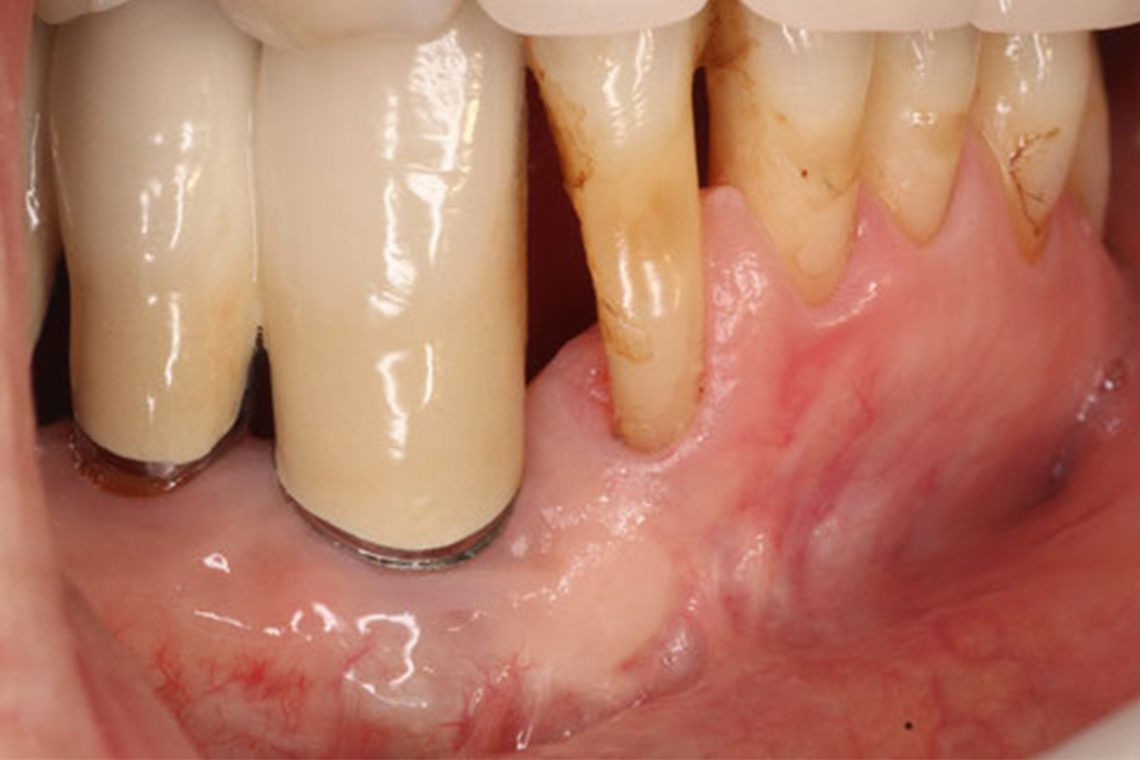

歯周病が進むと、歯を支えている骨が溶けて歯肉が下がり、歯が長く見えるようになります。また、歯がグラグラと揺れて歯と歯肉の隙間(歯周ポケット)も大きく開き、歯磨きが難しくなります。

この写真は、歯周病により数本の歯を失った患者さまのものです。当院で歯周病の治療とインプラント埋入治療も受けられました。そのため食事が不自由なくできるところまで回復し、その後も定期検診を受けて20年以上も健康的な歯を維持しています。